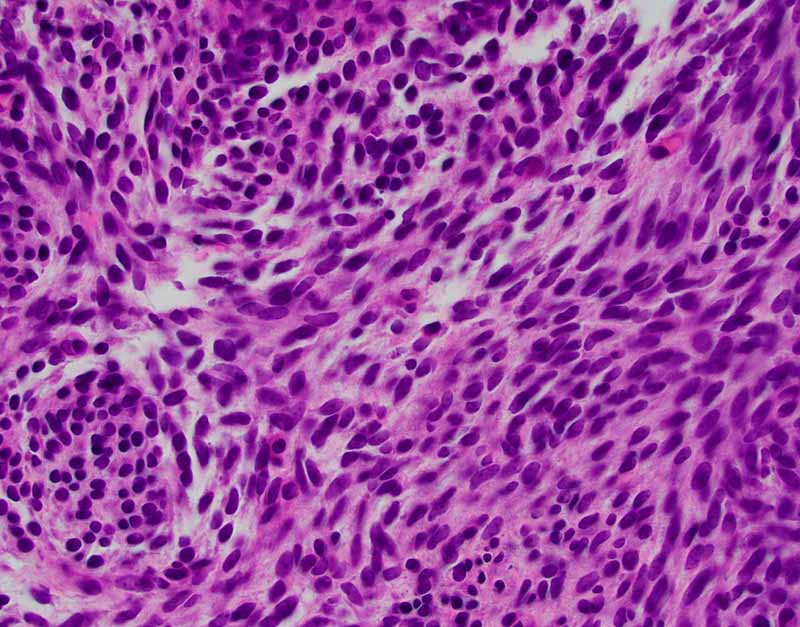

For Comparison: The following images were obtained from the FNA and core biopsy of a monophasic spindle cell synovial sarcoma. In general, the nuclei are rather monotonous and small. They are typically elongated and are very adhesive to each other. Typically, the amount of cytoplasm is minimal or most of the cells are naked nuclei. This case has SS18 rearrangment on FISH.

Synovial sarcomas span the spectrum from monophasic fibrous type to biphasic type with both distinct epithelial and spindle cell components in varying proportion, to epithelial-predominant type to poorly differentiated (round cell) type. Both the epithelial-predominant type and poorly differentiated type are uncommon. Monophasic fibrous type is the most common.

Monophasic fibrous synovial sarcoma is typically composed of monotonous solid sheets of small spindle cells with indistinct cytoplasmic membrane and small hyperchromatic nuclei without nucleoli. Vague palisading arrangement can be present. Usually, there is no intervening collagen fibers. Some foci of epithelioid morphology can be seen. Secondary changes such as calcifications and myxoid changes as seen in the spindle cell component of the biphasic type can also be found. Staghorn shaped blood vessels similar to those in hemangiopericytoma can be part of the histopathologic picture.